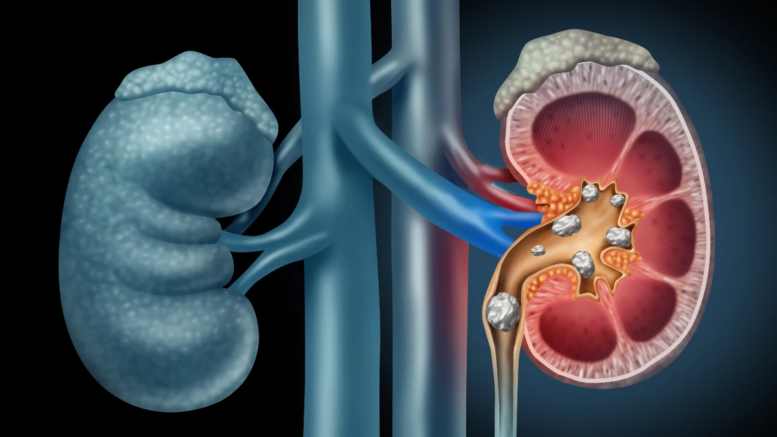

La malattia renale cronica oggi colpisce 850 milioni di persone in tutto il mondo e rappresenta l’ottava causa di morte e, se non affrontata, si prevede che entro il 2040 diventerà la quinta causa di abbassamento dell’aspettativa di vita.

L’obiettivo è sensibilizzare la gente sull’importanza dei reni e sulla necessità di arrivare a una diagnosi precoce per poter trattare adeguatamente la patologia. Si stima che la malattia renale cronica colpisca circa 800 milioni al mondo di persone; se non diagnosticata e trascurata può progredire fino all’insufficienza renale. Si prevede che entro il 2040 la patologia diventerà la quinta causa di riduzione di aspettativa di vita”.

La malattia renale cronica è una patologia complessa e invalidante che a causa della mancanza di sintomi viene diagnosticata tardivamente quando è già in stadio avanzato. In Italia e nel mondo circa il 10% della popolazione adulta ne è affetta e la maggior parte non ne è consapevole.

Gli esperti spiegano che “Si può perdere fino al 60-80% della funzionalità renale prima che si manifesti qualsiasi sintomo, momento in cui l’efficacia terapeutica si riduce notevolmente e la terapia sostitutiva diventa sempre più probabile”.

Negli ultimi 30 anni, il numero di nuovi casi di dialisi è aumentato del 43%. Contestualmente è aumentata del 41% la mortalità relativa alla MRC, e si stima che nel 2040 sarà la quinta causa di morte nel mondo.